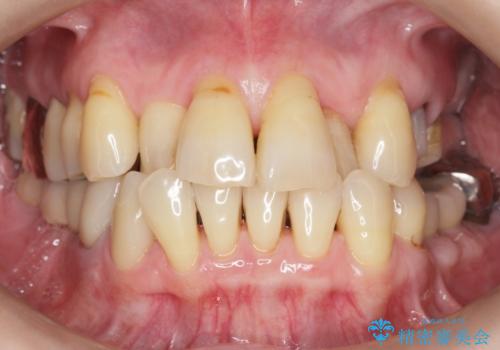

奥歯の違和感 再根管治療 40代女性

- 奥歯の違和感を主訴に来院された患者様です。

精査したところ、左上の大臼歯2本(左上67)が欠損しており、左上の小臼歯2本(左上45)は根が短く動揺があり根尖病変を認めました。

「大臼歯は入れ歯かインプラントを検討しているがまだやりたくないため、小臼歯のみを治療してほしい」との患者様のご希望により、

相談を重ねた上で小臼歯2本の再根管治療と連結補綴を行いました。

大臼歯がないため小臼歯に負担がかかりやすいことによるリスクを説明し、ご理解頂いた上で治療を行いました。

気にされていた歯の動揺や違和感がなくなり、喜んで頂けました。

モチベーションがあがり、大臼歯欠損部位の治療に関しても前向きに検討して下さるとの事でした。